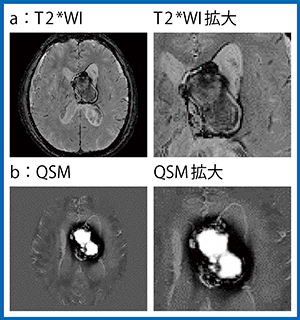

単純CTでは腫瘍の大部分は淡い高信号で,辺縁の一部に塊状の強い高信号が認められたが(図1 a),同部位はT1強調画像(T1WI)(b),T2強調画像(T2WI)(c)でも出血/石灰化の区別が困難だった。また,T2*強調画像(T2*WI)でも,時期の異なる出血があることは指摘できるものの,石灰化の有無は判断できなかった(図2 a)。これに対してQSMでは,腫瘍の中央は高信号に描出されるため出血が,辺縁は非常に低信号であることから磁化率の低い石灰化が示唆された(図2 b)。また,CT(図1 a)で強い高信号を示した部分は,QSM(図2 b)で低信号に描出されたことから石灰化と考えられた。MRIでは出血と石灰化の鑑別はQSMでしかできないため,質的診断にQSMは非常に役立った。

図2 症例1の磁化率画像